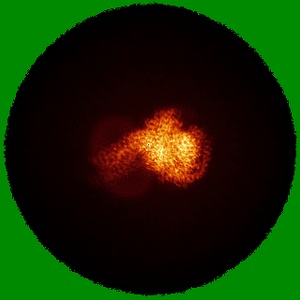

Cryo-EM structure of the anamorelin-bound ghrelin receptor and Gq complex

Single-particle2.9 Å

Sample: Anamorelin-bound ghrelin receptor in complex with Gq